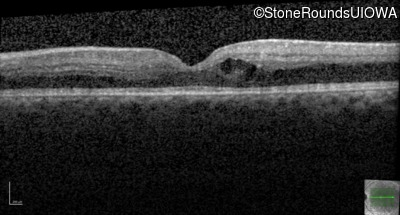

Optical Coherence Tomography - Left - 20/20 -3

Exemplar / OCT Stack

OCT Stack